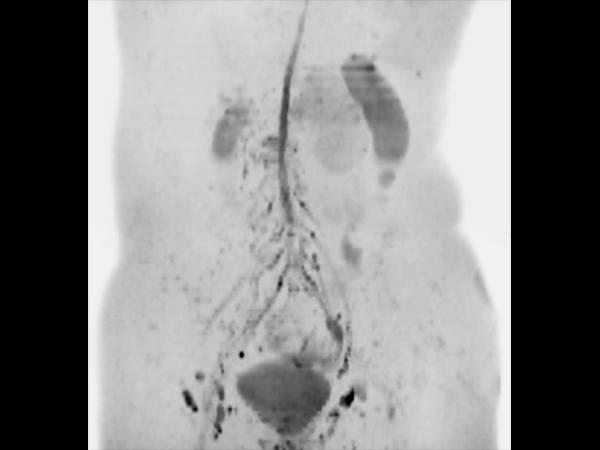

Coronal DWIBS (MIP) dS SENSE = 4, MobiView